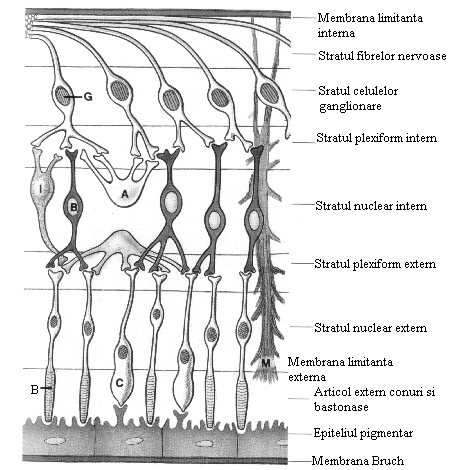

RETINA - PATOLOGIA RETINEI - AFECTIUNILE RETINEI

RETINA Retina este membrana nervoasa a ochiului, denumirea provenind din comparatia cu o retea localizata in jurul vitrosului. Embriologie Retina are origine ectodermica, iar vasele si tecile gliaCiteste tot ... 7803 cuvinte

Dimensiune mare

+ cu imagini |